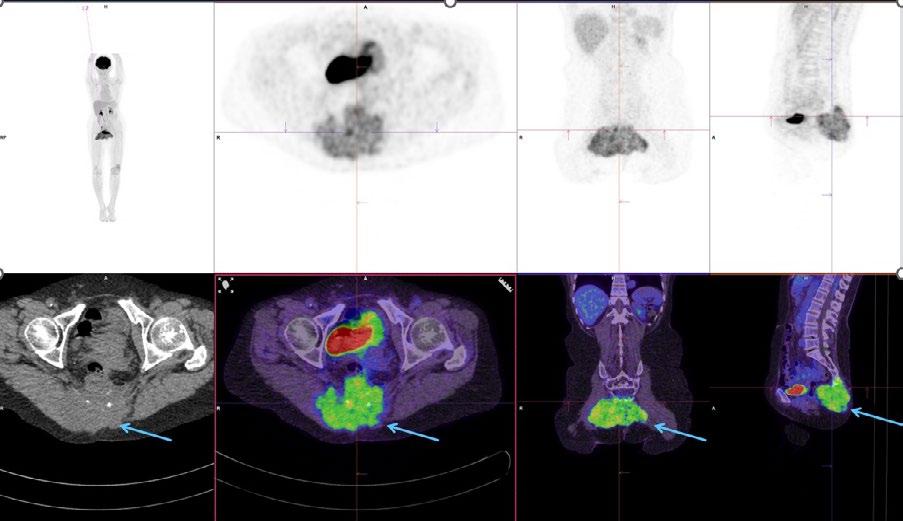

Issuu converts static files into: digital portfolios, online yearbooks, online catalogs, digital photo albums and more. Sign up and create your flipbook.